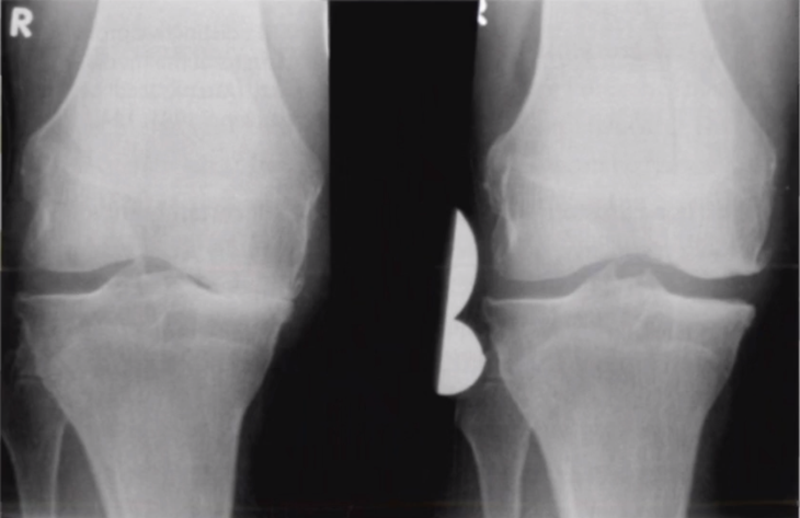

二、单髁置换的适应证——外翻应力片

屈曲20°外翻应力:看外侧软骨

外翻应力片可以辅助评价外侧间室关节软骨厚度是否正常,以及内侧副韧带功能是否完整。外侧全层软骨、外侧有骨赘的情况下都不是禁忌证,如外侧出现软骨磨损则为禁忌证。

外翻应力片还可以观察内侧间隙,如内侧副韧带出现挛缩,间隙狭窄,那么此时不适合单髁。

检查时注意X线的投照角度要平行于关节线方向,以保证准确。

可以矫正畸形,恢复关节间隙和MCL张力

AMOA的X线正位的表现